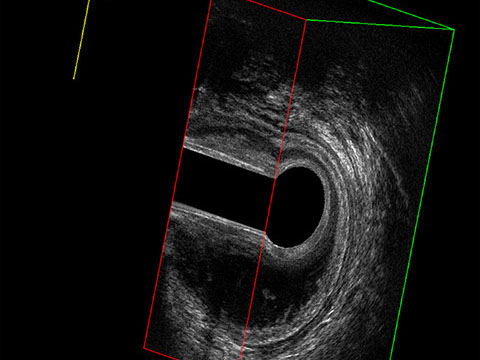

Sezione Longitudinale 3D con Tramite Fistoloso Intersfinterico Basso Anteriore Semplice

L’ecografia transanale è un esame diagnostico per immagini che consiste nell’introduzione di un trasduttore ad ultrasuoni. Le immagini qualitativamente migliori del canale anale sono ottenute usando un trasduttore rotante, montato in un manipolo rigido, che fornisce un’immagine a 360°. Con le apparecchiature più moderne è anche possibile ottenere immagini tridimensionali.

L’ecografia transanale permette di distinguere la sottomucosa che riveste il canale anale, lo sfintere anale interno, e lo sfintere anale esterno.

Proctal dispone di apparecchiatura per ecografia endoanale 3D con sonda rotante.